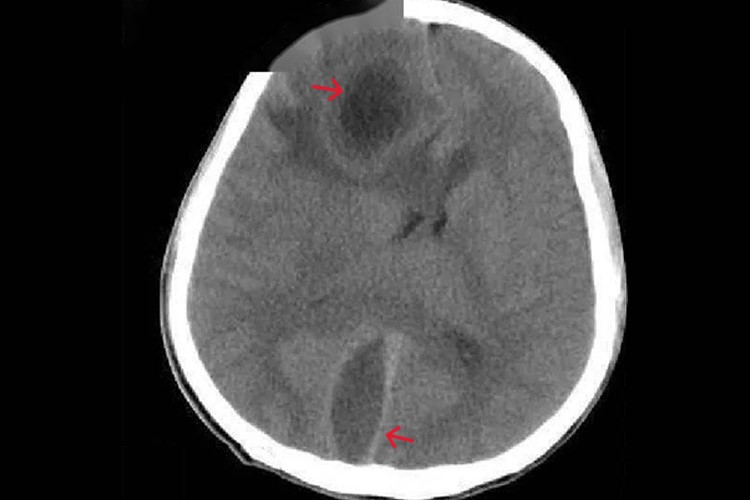

CT增强检查可见病变呈不同形式强化,均匀性强化见于脑膜瘤、转移瘤、神经鞘瘤、动脉瘤和肉芽肿等;非均匀性强化见于胶质瘤、血管畸形等;环形强化见于脑脓肿、结核瘤、胶质瘤、转移瘤等;无强化见于脑炎、囊肿,水肿等。

颅脑CT增强扫描可使病灶与邻近正常组织的密度对比差异增大,以提高病变的检出率及定性诊断的准确率。增强扫描主要用于脑肿瘤、颅内感染及脑血管疾病(如动脉瘤、血管畸形)等。

颅脑外伤患者CT平扫正常但临床疑为颅内等密度血肿者,及原因不明的蛛网膜下腔出血3天以上者,也应行增强扫描。急性颅脑外伤、急性脑卒中、先天性颅脑畸形一般只行平扫,无需增强扫描。